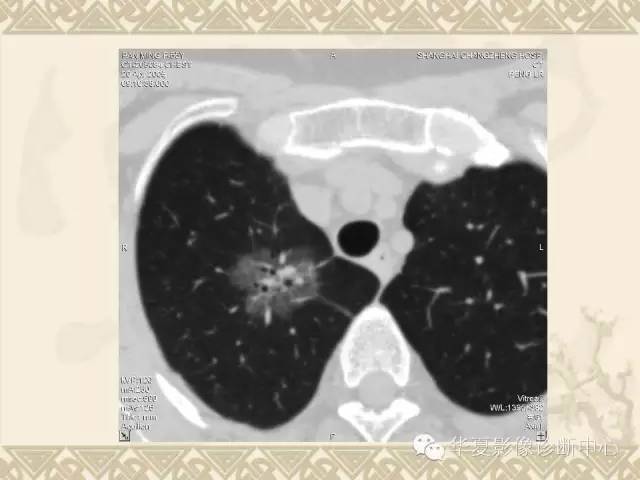

肺内磨玻璃样结节的影像诊断与处理对策